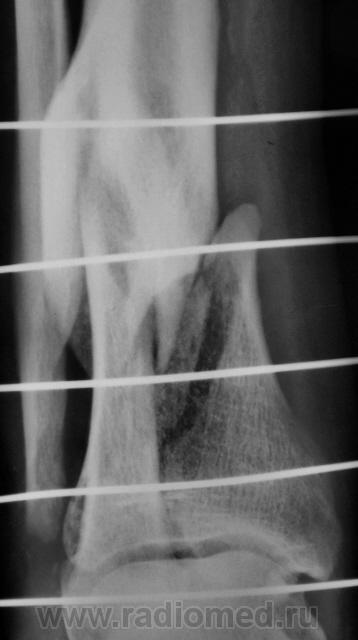

Травма. Пациент доставлен в рентгеновский кабинет ургентно.

Это она. Б/берцовка какая-то мутная.

В колесо телеги затянуло.

Судя по б/б кости не в первой.